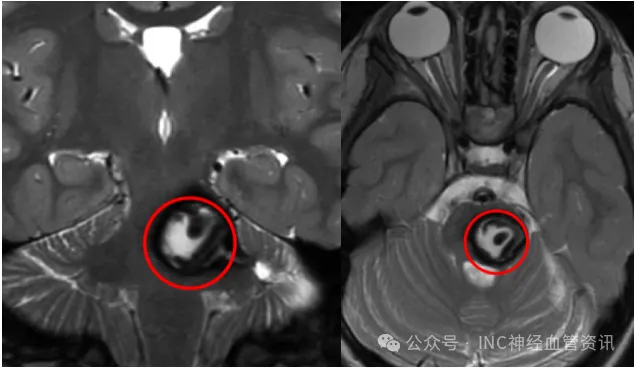

位于大脑核心区域第三脑室的巨大肿瘤,由INC巴特朗菲教授主刀...